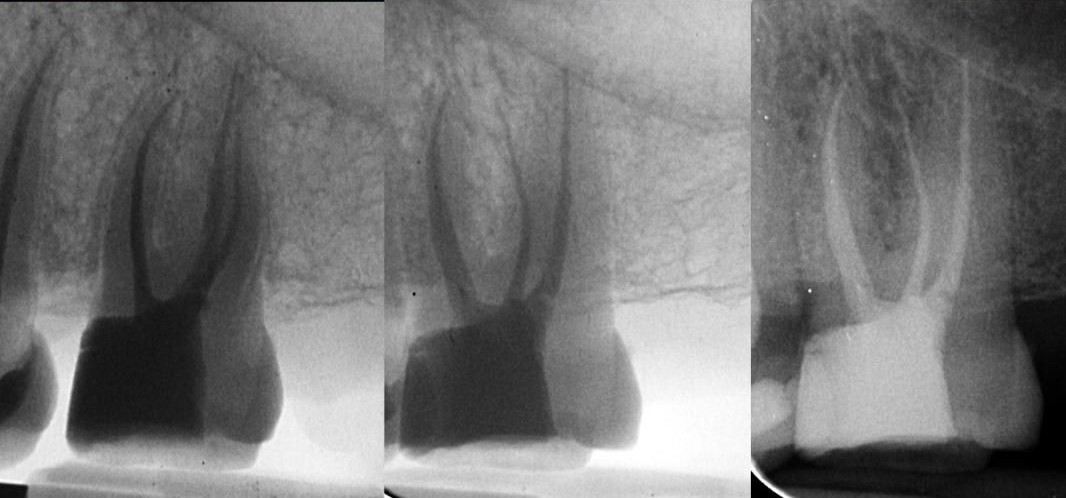

Maxillary molar with complex root canal anatomy featuring MB1 and MB2 canals that converge in the apical third.

Clinical Challenges

• Locating and carefully negotiating the often hidden MB2 canal.

• Safely managing the convergence of MB1 and MB2 canals in the apical third without creating transportation.

• Achieving a centered preparation while avoiding unnecessary dentin removal and preserving the original canal anatomy.

In this maxillary molar, the MB2 canal was meticulously located and negotiated. It joined the MB1 canal in the apical third, creating a complex converging anatomy. Even when canals merge, each requires full respect and proper management to ensure long-term success.

Shaping was carried out using the Denco Chameleon Dual Shaper. This system provided smooth, controlled cutting action combined with excellent safety features. The preparation remained perfectly centered throughout the procedure, with no evidence of transportation or excessive dentin sacrifice. The natural root canal anatomy was beautifully preserved from start to finish.